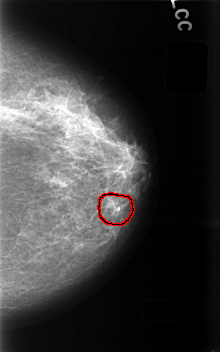

Digital Database for Screening Mammography

Volume: benign_13 Case: C-0487-1

C_0487_1.LEFT_CC

LEFT_CC LINES 4568 PIXELS_PER_LINE 2856 BITS_PER_PIXEL 12 RESOLUTION 50 OVERLAY

FILE: C_0487_1.LEFT_CC.OVERLAY

TOTAL_ABNORMALITIES 1

ABNORMALITY 1

LESION_TYPE CALCIFICATION TYPE PLEOMORPHIC DISTRIBUTION CLUSTERED

ASSESSMENT 3

SUBTLETY 4

PATHOLOGY BENIGN

TOTAL_OUTLINES 1

BOUNDARY